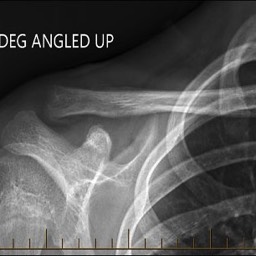

What do clavicle fractures look like on X-ray?

Below are examples of typical fractures that benefit from surgery.

Diagnosis of a distal clavicle fracture is made with history, then a plain xray of the clavicle and in a lot of cases a CT scan. With new 3D CT scan imaging, separation of bony fragments can be well visualised which helps for possible surgical planning.